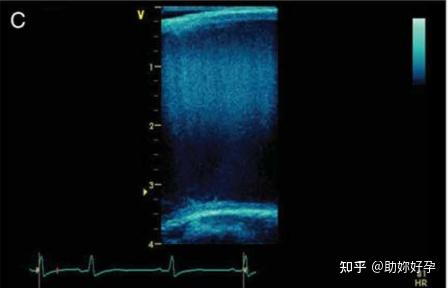

与上面由许多扫描线得到一帧图像以显示解剖结构不同的是,使用运动模式(M 模式)可以获得改进的时间分辨率,例如在评估瓣膜结构的运动时。在 M 模式下,结构以一个维度表示。时间分辨率定义为从一个脉冲到下一个脉冲所花费的时间,即脉冲重复周期(图 4B)。